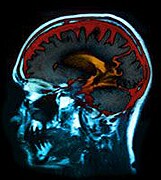

Obesity might also be behind the increase, researchers say